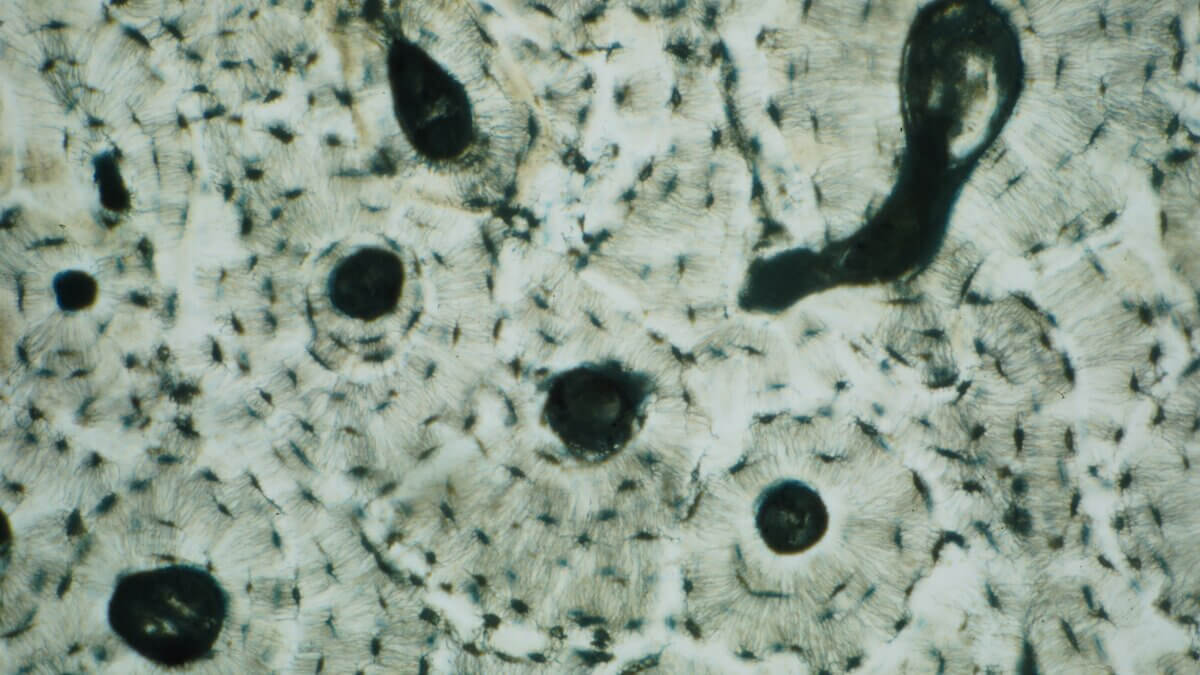

Lamellenknochen ist eine histologische Kategorie und hat nichts mit dem makroskopischen Aspekt des Knochens zu tun. Er findet sich in Form von Knochenlamellen sowohl in der Substantia compacta als auch in der Spongiosa. In der Spongiosa sieht man parallel zur Oberfläche angeordnete Lamellen, in der Kompakta Lamellen, die – organisiert zu so genannten Osteonen – konzentrisch um ein zentrales Blutgefäß angeordnet sind.

- Konzentrische Lamellen: Hier laufen die Lamellen um einen zentralen Gefäßkanal (Havers-Kanal) und bilden so das Osteon als Grundbaustein der Kompakta.